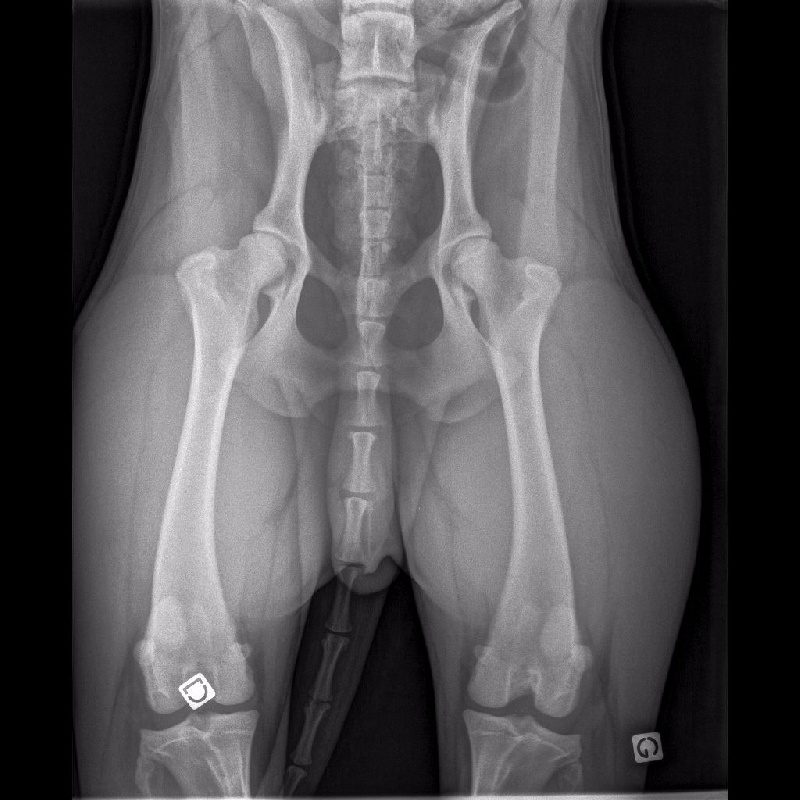

HANCHES